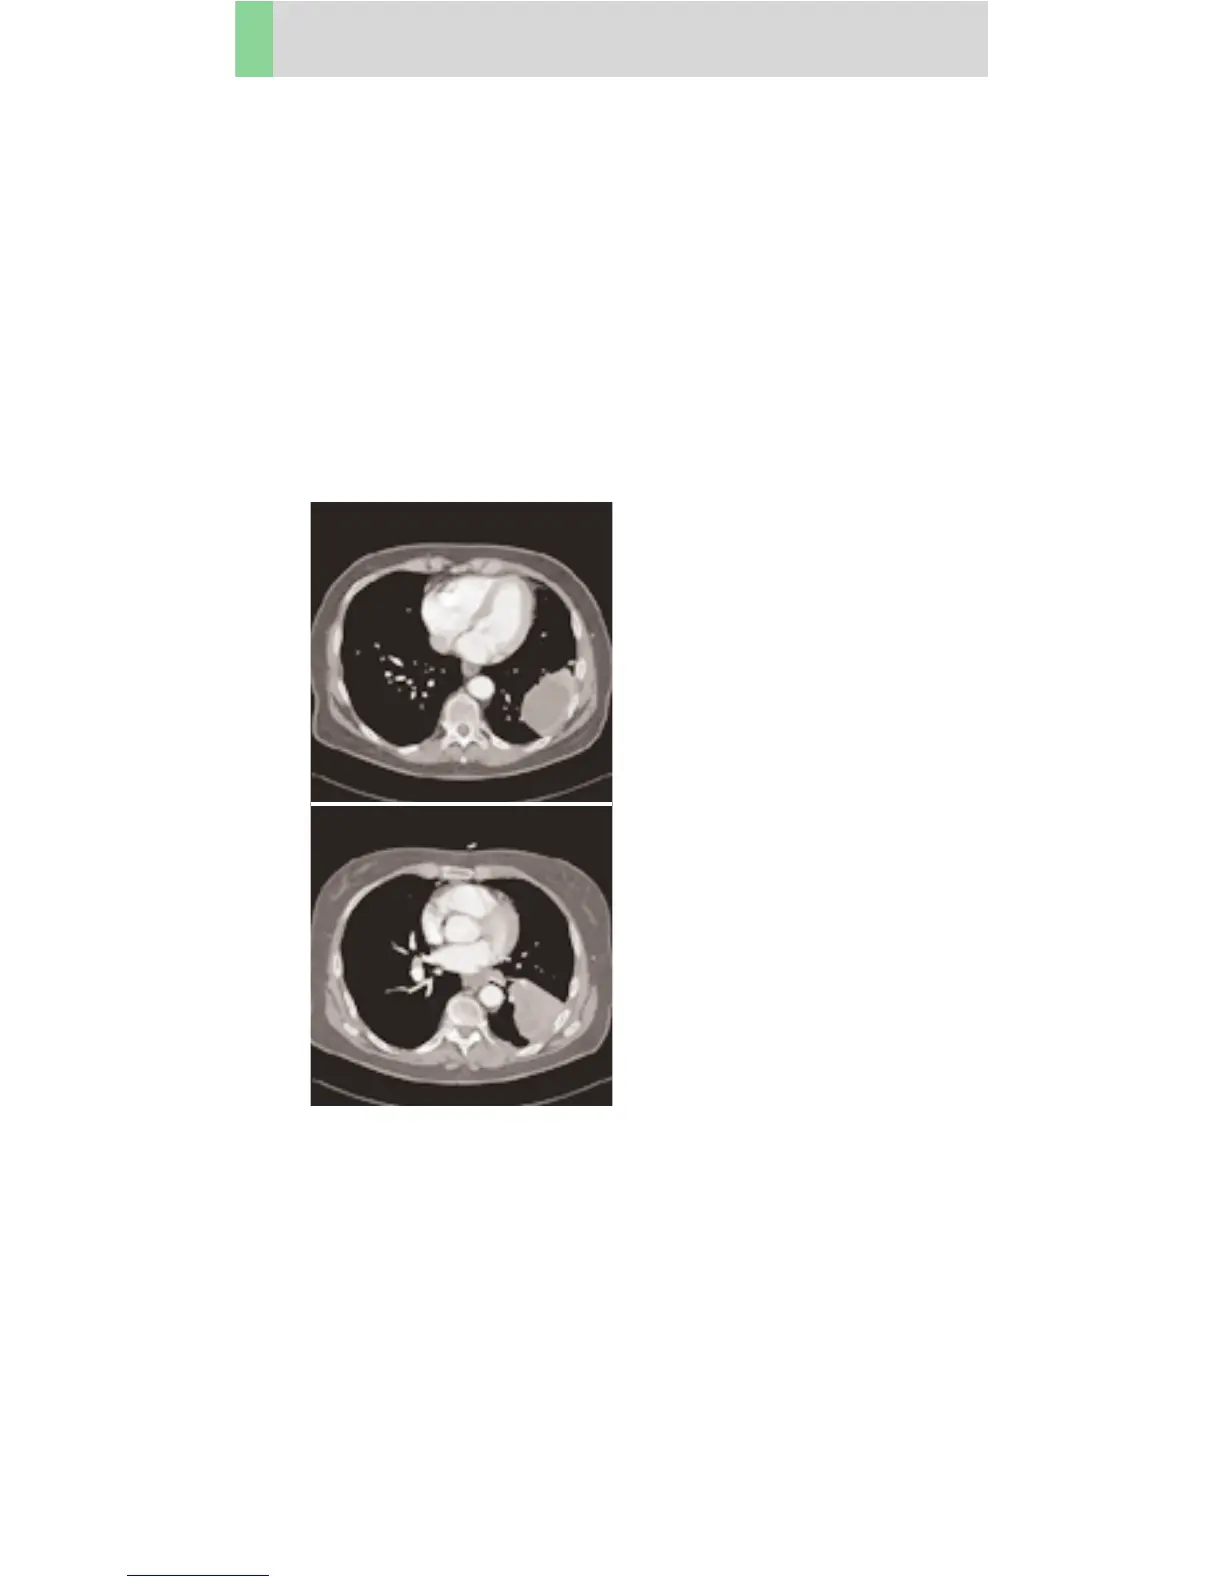

Thorax

ThoraxRoutine06s

Routine spiral studies for the region of thorax, e. g.

screening of tumors, metastases, lymphoma, lymph

nodes, vascular anomalies etc., using a 0.6 sec.

rotation time.

A range of 30 cm will be covered in 12.5 sec.